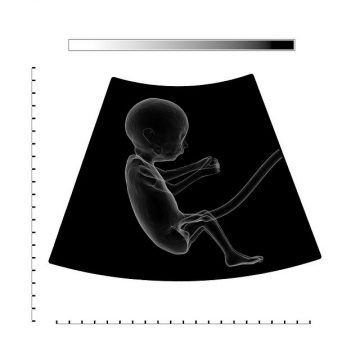

When a baby is still in the womb, the umbilical cord is a vital lifeline that connects them to the mother. Unfortunately, there are many ways that the umbilical cord could cause harm during childbirth, especially when medical malpractice is involved. Here is some more information about umbilical cord injuries.

Compressed Umbilical Cord

Another issue is that the umbilical cord can become compressed. This not just affects the of oxygen that can reach the infant, yet it can likewise cut off blood and nutrient stream for the infant. At times, this can bring about harm to the brain. In other, increasingly extreme issues, fetal demise is a chance. Children who do endure the remainder of the work process may experience the ill effects of different issues such as developmental issues, wounds associated with an emergency C-section, and heart variations from the norm.